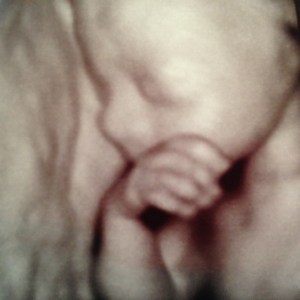

(and yes, these are actual 3D ultrasound pictures of Ella – she looks great already!)

Awesome! I love the shot of her covering her eyes as if to say, “I can’t even HANDLE this.”

RIGHT?! that’s my favorite, too. :)